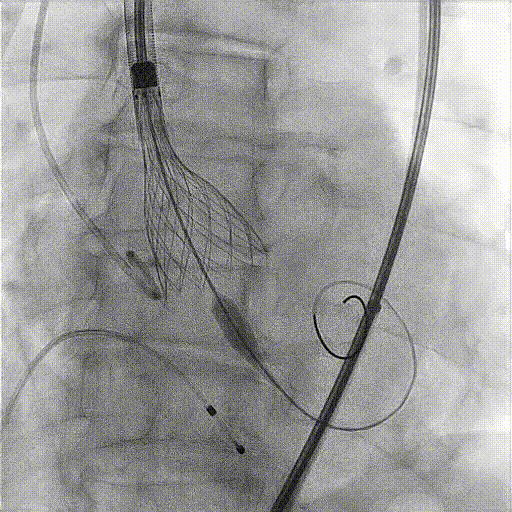

PCI植入过程:

术中影像:

Quantum 球囊扩张

复查冠脉造影血流通畅